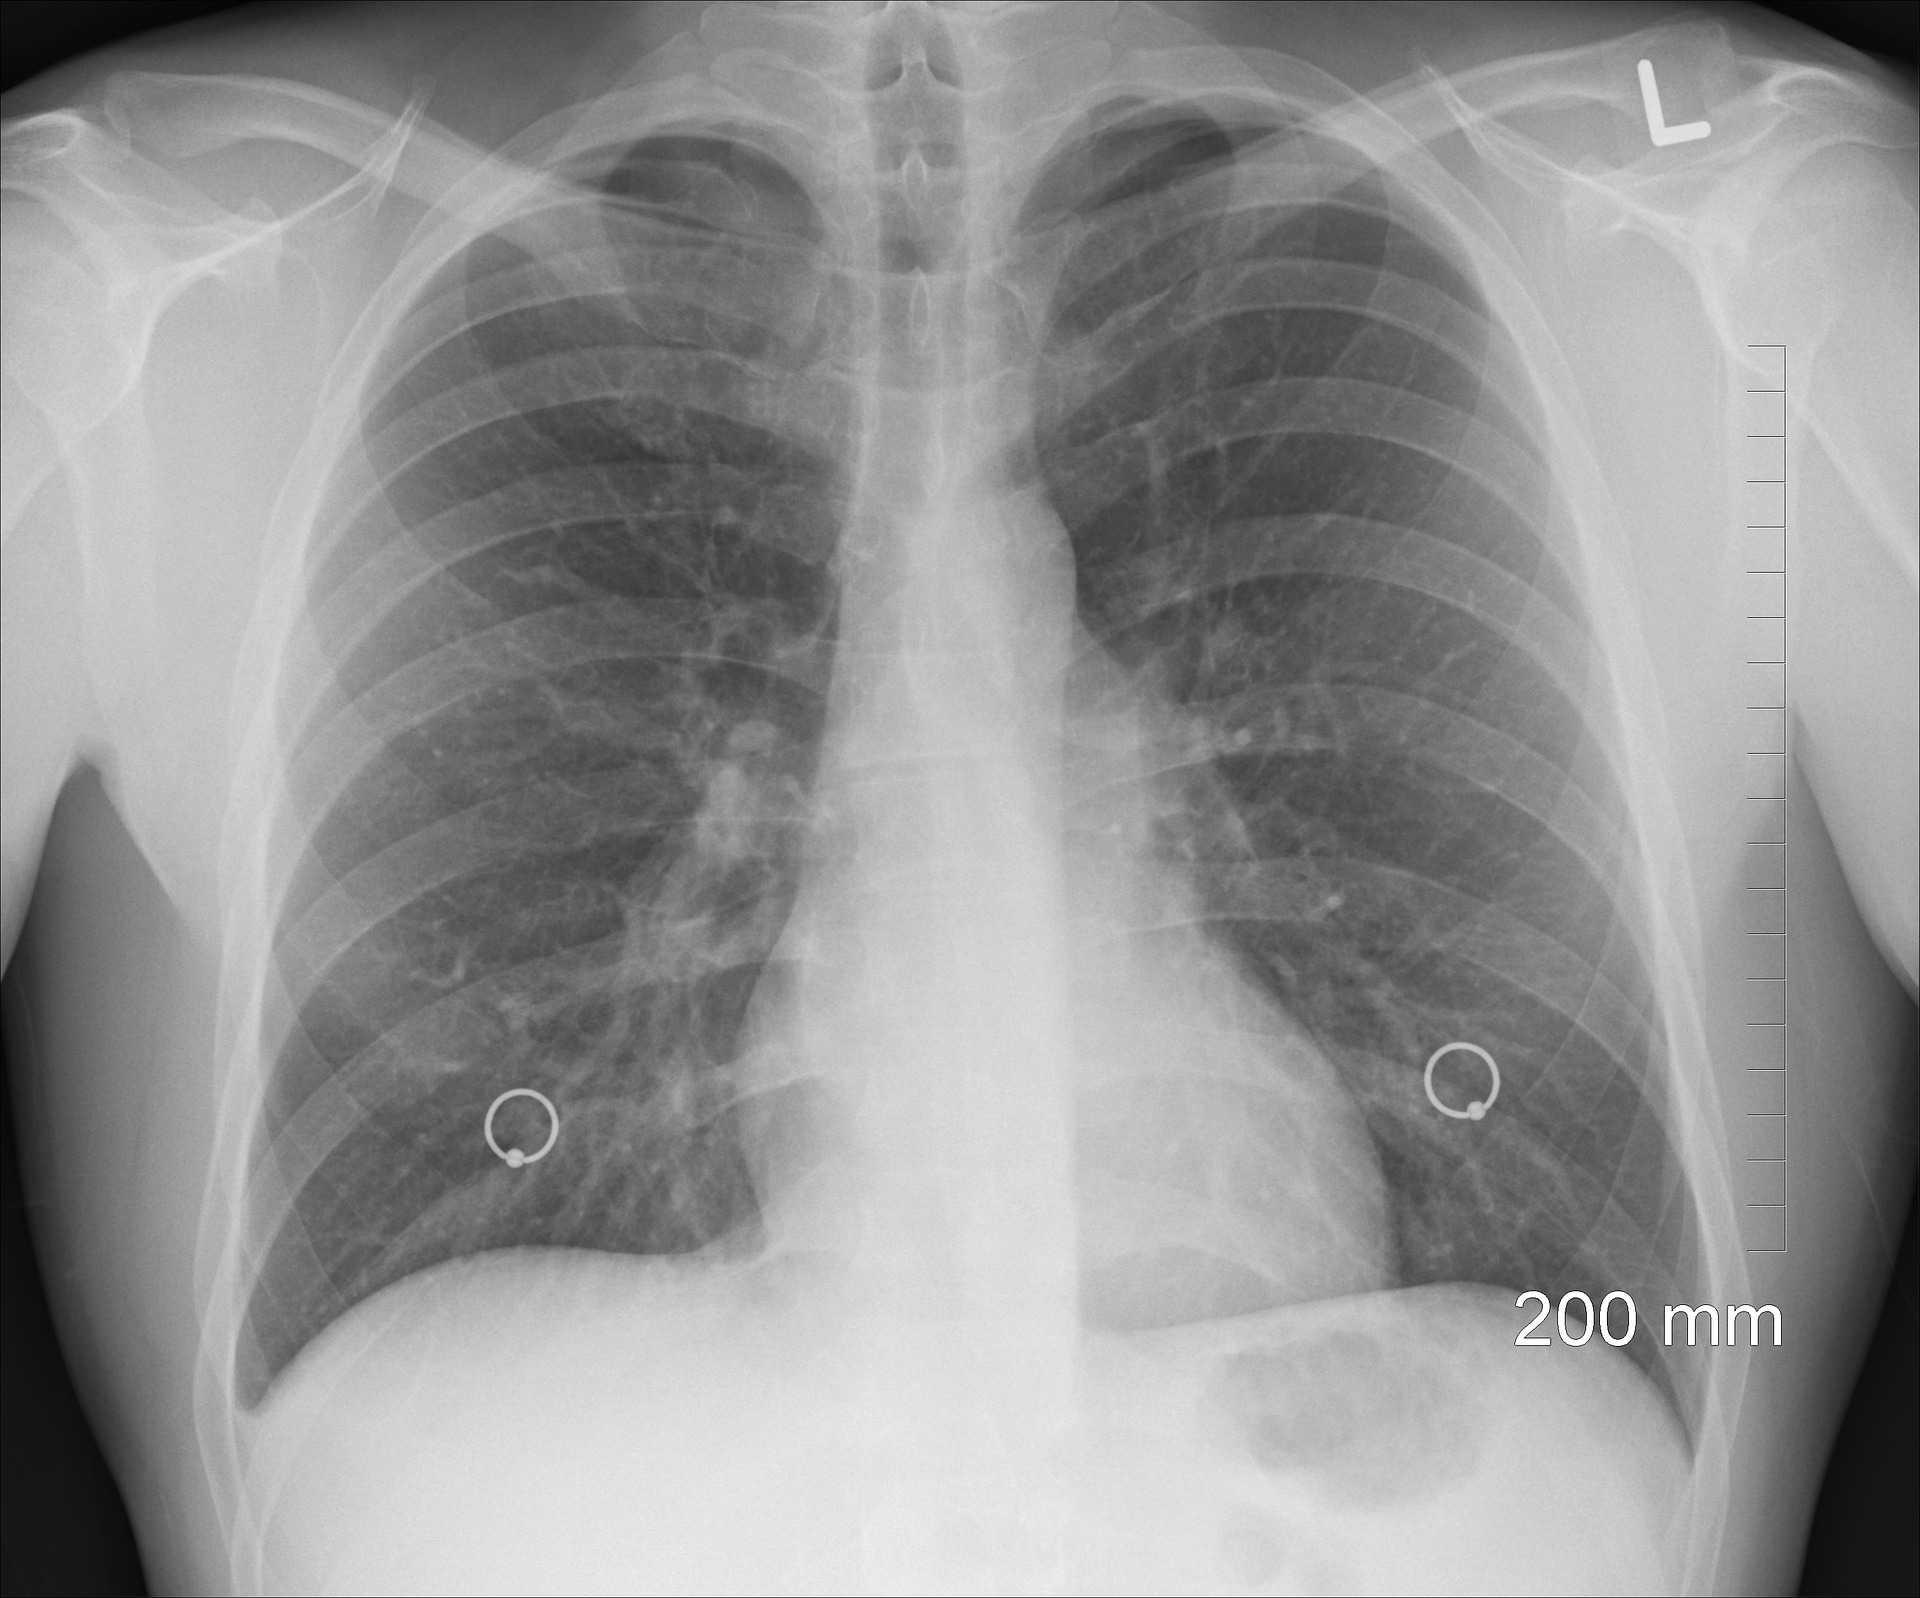

"Mayapada Hospital Surabaya baru-baru ini kedatangan pasien lansia wanita usia 70 tahun. Pasien tersebut datang dengan keluhan batuk dan sesak nafas yang tak kunjung membaik tanpa riwayat merokok. Pasien segera dilakukan pemeriksaan rontgen paru dan CT Scan paru dengan kontras. Ditemukan tumor pada paru sebelah kanan serta cairan di rongga selaput pembungkus paru di area tersebut," kata dr. Bambang dalam keterangannya pada Sabtu.Dokter kemudian melakukan tindakan pengambilan cairan tersebut dan dilakukan tindakan bronkoskopi (biopsi paru) untuk memastikan status tumor paru tersebut apakah berbahaya atau tidaknya.

"Hasil biopsi dan CT Scan paru dari pasien wanita berumur 70 tahun tersebut, diketahui diagnosa pasien adalah kanker paru jenis Non Small Cell Lung Cancer - Adenocarcinoma stadium 4," katanya.